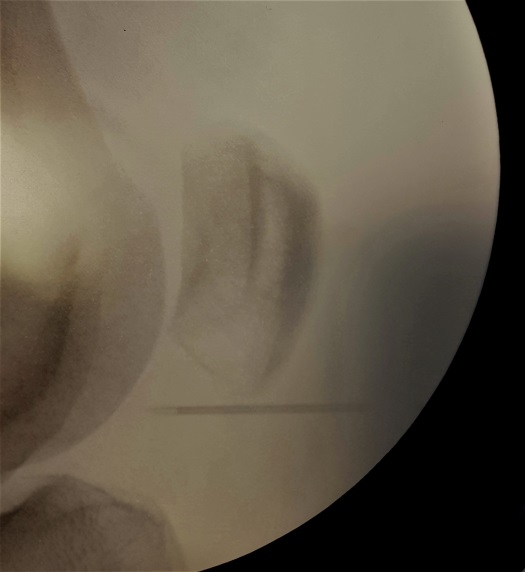

Foto 1. Aspect IRM: îngroşarea tendonului patelar + edem al grăsimii Hoffa + edem osos și o fractură trabeculară a polului inferior al patelei

Foto 2 și 3. Aspecte intraoperatorii: reperarea radiologică a polului inferior al patelei; imagine artroscopică după excizia parțială a grăsimii Hoffa și rezecția polului inferior al patelei cu shaverul.